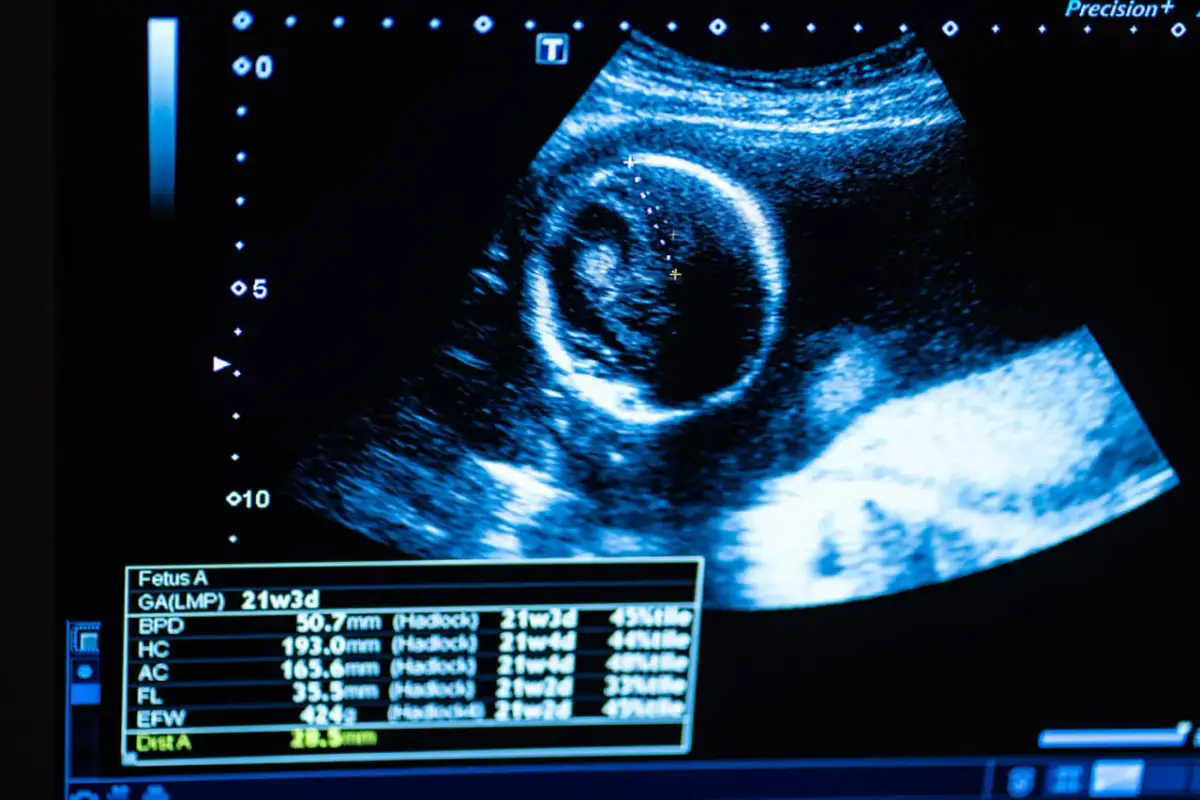

USG w II trymestrze (18-22 tydzień): Wielki przegląd anatomii Twojego maluszka

Badanie ultrasonograficzne w drugim trymestrze, często nazywane USG połówkowym, jest niezwykle ważnym etapem diagnostyki prenatalnej. Przeprowadza się je zazwyczaj między 18. a 22. tygodniem ciąży i pozwala na bardzo szczegółową ocenę anatomii płodu. To właśnie podczas tego badania lekarz dokładnie analizuje budowę wszystkich narządów i układów, aby wykluczyć obecność wad wrodzonych.

Biometria płodu, czyli sprawdzamy, czy maluch prawidłowo przybiera na wadze

Biometria płodu to zestaw pomiarów antropometrycznych, które pozwalają ocenić, czy dziecko rozwija się prawidłowo i przybiera na wadze zgodnie z normami dla danego wieku ciążowego. Lekarz mierzy między innymi obwód główki, brzuszek oraz długość kości udowej. Na podstawie tych pomiarów szacowana jest masa płodu. Prawidłowa biometria jest kluczowa dla oceny dobrostanu dziecka.